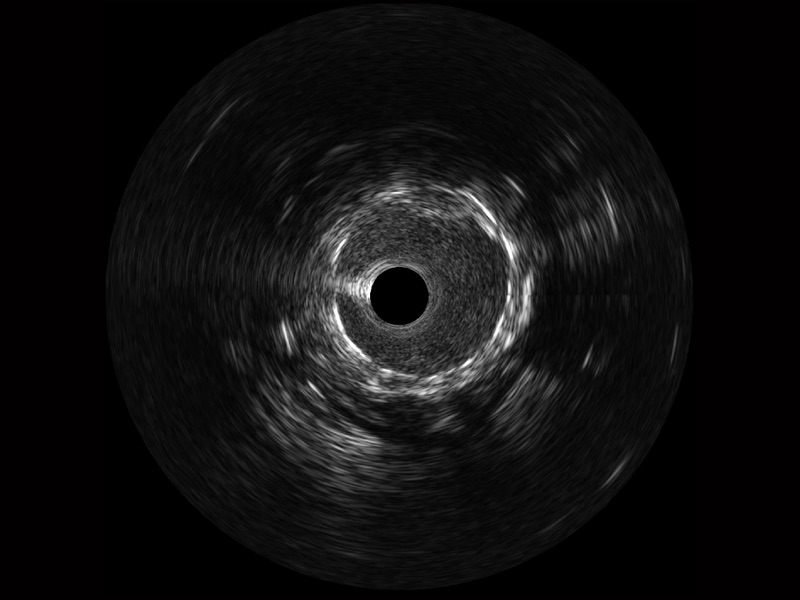

開(kāi)立寬頻IVUS圖像

傳統(tǒng)IVUS圖像

對(duì)比傳統(tǒng)IVUS導(dǎo)管成像,開(kāi)立寬頻IVUS圖像的近場(chǎng)支架梁顯影更細(xì)膩,遠(yuǎn)場(chǎng)中膜外血管仍清晰可辨,兼顧遠(yuǎn)中近,兼顧分辨力與穿透深度